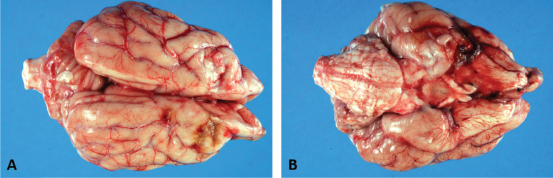

Fig. 3. Dorsal (A) and ventral (B) gross views of the brain showing focally extensive thrombosis of the right ventral cerebral artery resulting in an ischemic encephalopathy to the regions supplied by this artery and the loss of tissue which manifested as the depressed areas of malacia on the dorsal view.

Necropsy findings included granulomatous myositis with fibrosis overlying the ventral aspect of the right masseter muscle, extending into the buccal submucosa and concurrent moderate multifocal chronic granulomatous lymphadenitis of the maxillary lymph nodes. Two lesions consistent with encephalomalacia were identified in the cerebral cortex: the first, a 1.5 cm × 1 cm, irregular, focal tan-brown depressed soft area within the right rostral and dorsal cerebral cortex just caudal to the median raphe, and the second, a 1 cm × 1 cm area associated with the left rostral cerebral cortex (Fig. 3). Severe, multifocal malacia was present in both the dorsal right hippocampus and right caudate nucleus. A firm thrombus was present in the rostral right cerebral artery of the right cerebrum (Fig. 3). Finally, along the right ventral calvarium, presumptive chronic multifocal, focally extensive proliferative osteitis was identified with compression and replacement of portions of the right optic nerve and chiasm (Fig. 4). No other gross lesions consistent with L. giganteum infection were identified outside the CNS and soft tissues of the head in a complete necropsy.

Within the brain, there was subacute to chronic, multifocal to coalescing, severe, granulomatous, lymphoplasmacytic, and neutrophilic meningoencephalitis predominantly of the right telencephalon and diencephalon associated with arteritis and arterial thrombosis of the right cerebral artery. Moderate chronic multifocal encephalomalacia was present bilaterally within the rostral cerebrum (Fig. 6). Numerous intralesional hyphae were identified in all lesions. Culture yielded a hyphal organism with morphologic features consistent with an oomycete, and PCR sequencing was consistent with the previously obtained L. giganteum isolate from this dog.

This case report represents an uncommon presentation of lagenidiosis. Medical management with mefenoxam, minocycline, prednisone, and HBOT produced unknown effects given the rapid progression. This case suggests that the organism invaded through the ventral calvarium, gained access to local arteries producing thrombi with secondary acute ischemic encephalopathy and caused severe meningoencephalitis, resulting in the patient’s acute neurologic signs. The disparity between the clinical neurolocalization and necropsy findings is best explained by the diffuse inflammatory changes and vascular thrombi with secondary ischemic sequelae affecting more areas of the brain than observed. The acute blindness was likely caused by the encephalitis and ischemia in the brain, but lesions in the right optic nerve could have been contributory. The proprioceptive deficits on the left side are best explained by a right cortical lesion. The cause for the head tilt is unexplained; ischemic damage to the brainstem is possible and it is also possible that there was undetected asymmetric visual function that could have resulted in a compensatory head tilt. No causes of peripheral vestibular disease were identified on necropsy. The multiple foci of malacia in the brain away from the site of the lesion demonstrate the distant effects of the observed thrombosis.